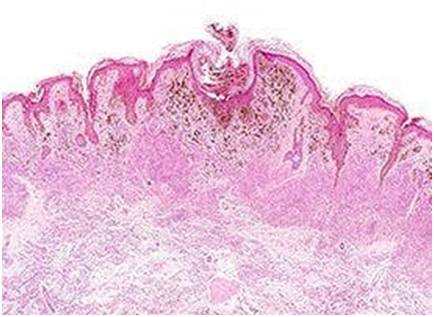

Oncolytic viruses, as these cancer cell-infecting viruses are known, thrive inside cancer cells. There, they replicate rapidly, destroying the cells by breaking them open and also exposing the cell’s contents to the immune system. Not only do these viruses naturally disrupt cancer, but they can be modified to carry other genes directly into cancer cells that boost the treatment’s ability to destroy tumors.

The researchers started by trying to identify the most potent immune-suppressing signals in the tumor. To do so, they took advantage of a mouse model of head and neck cancer that was resistant to some forms of immunotherapy. A series of experiments using an unmodified oncolytic virus pointed at TGF-beta as a critical source of that resistance.